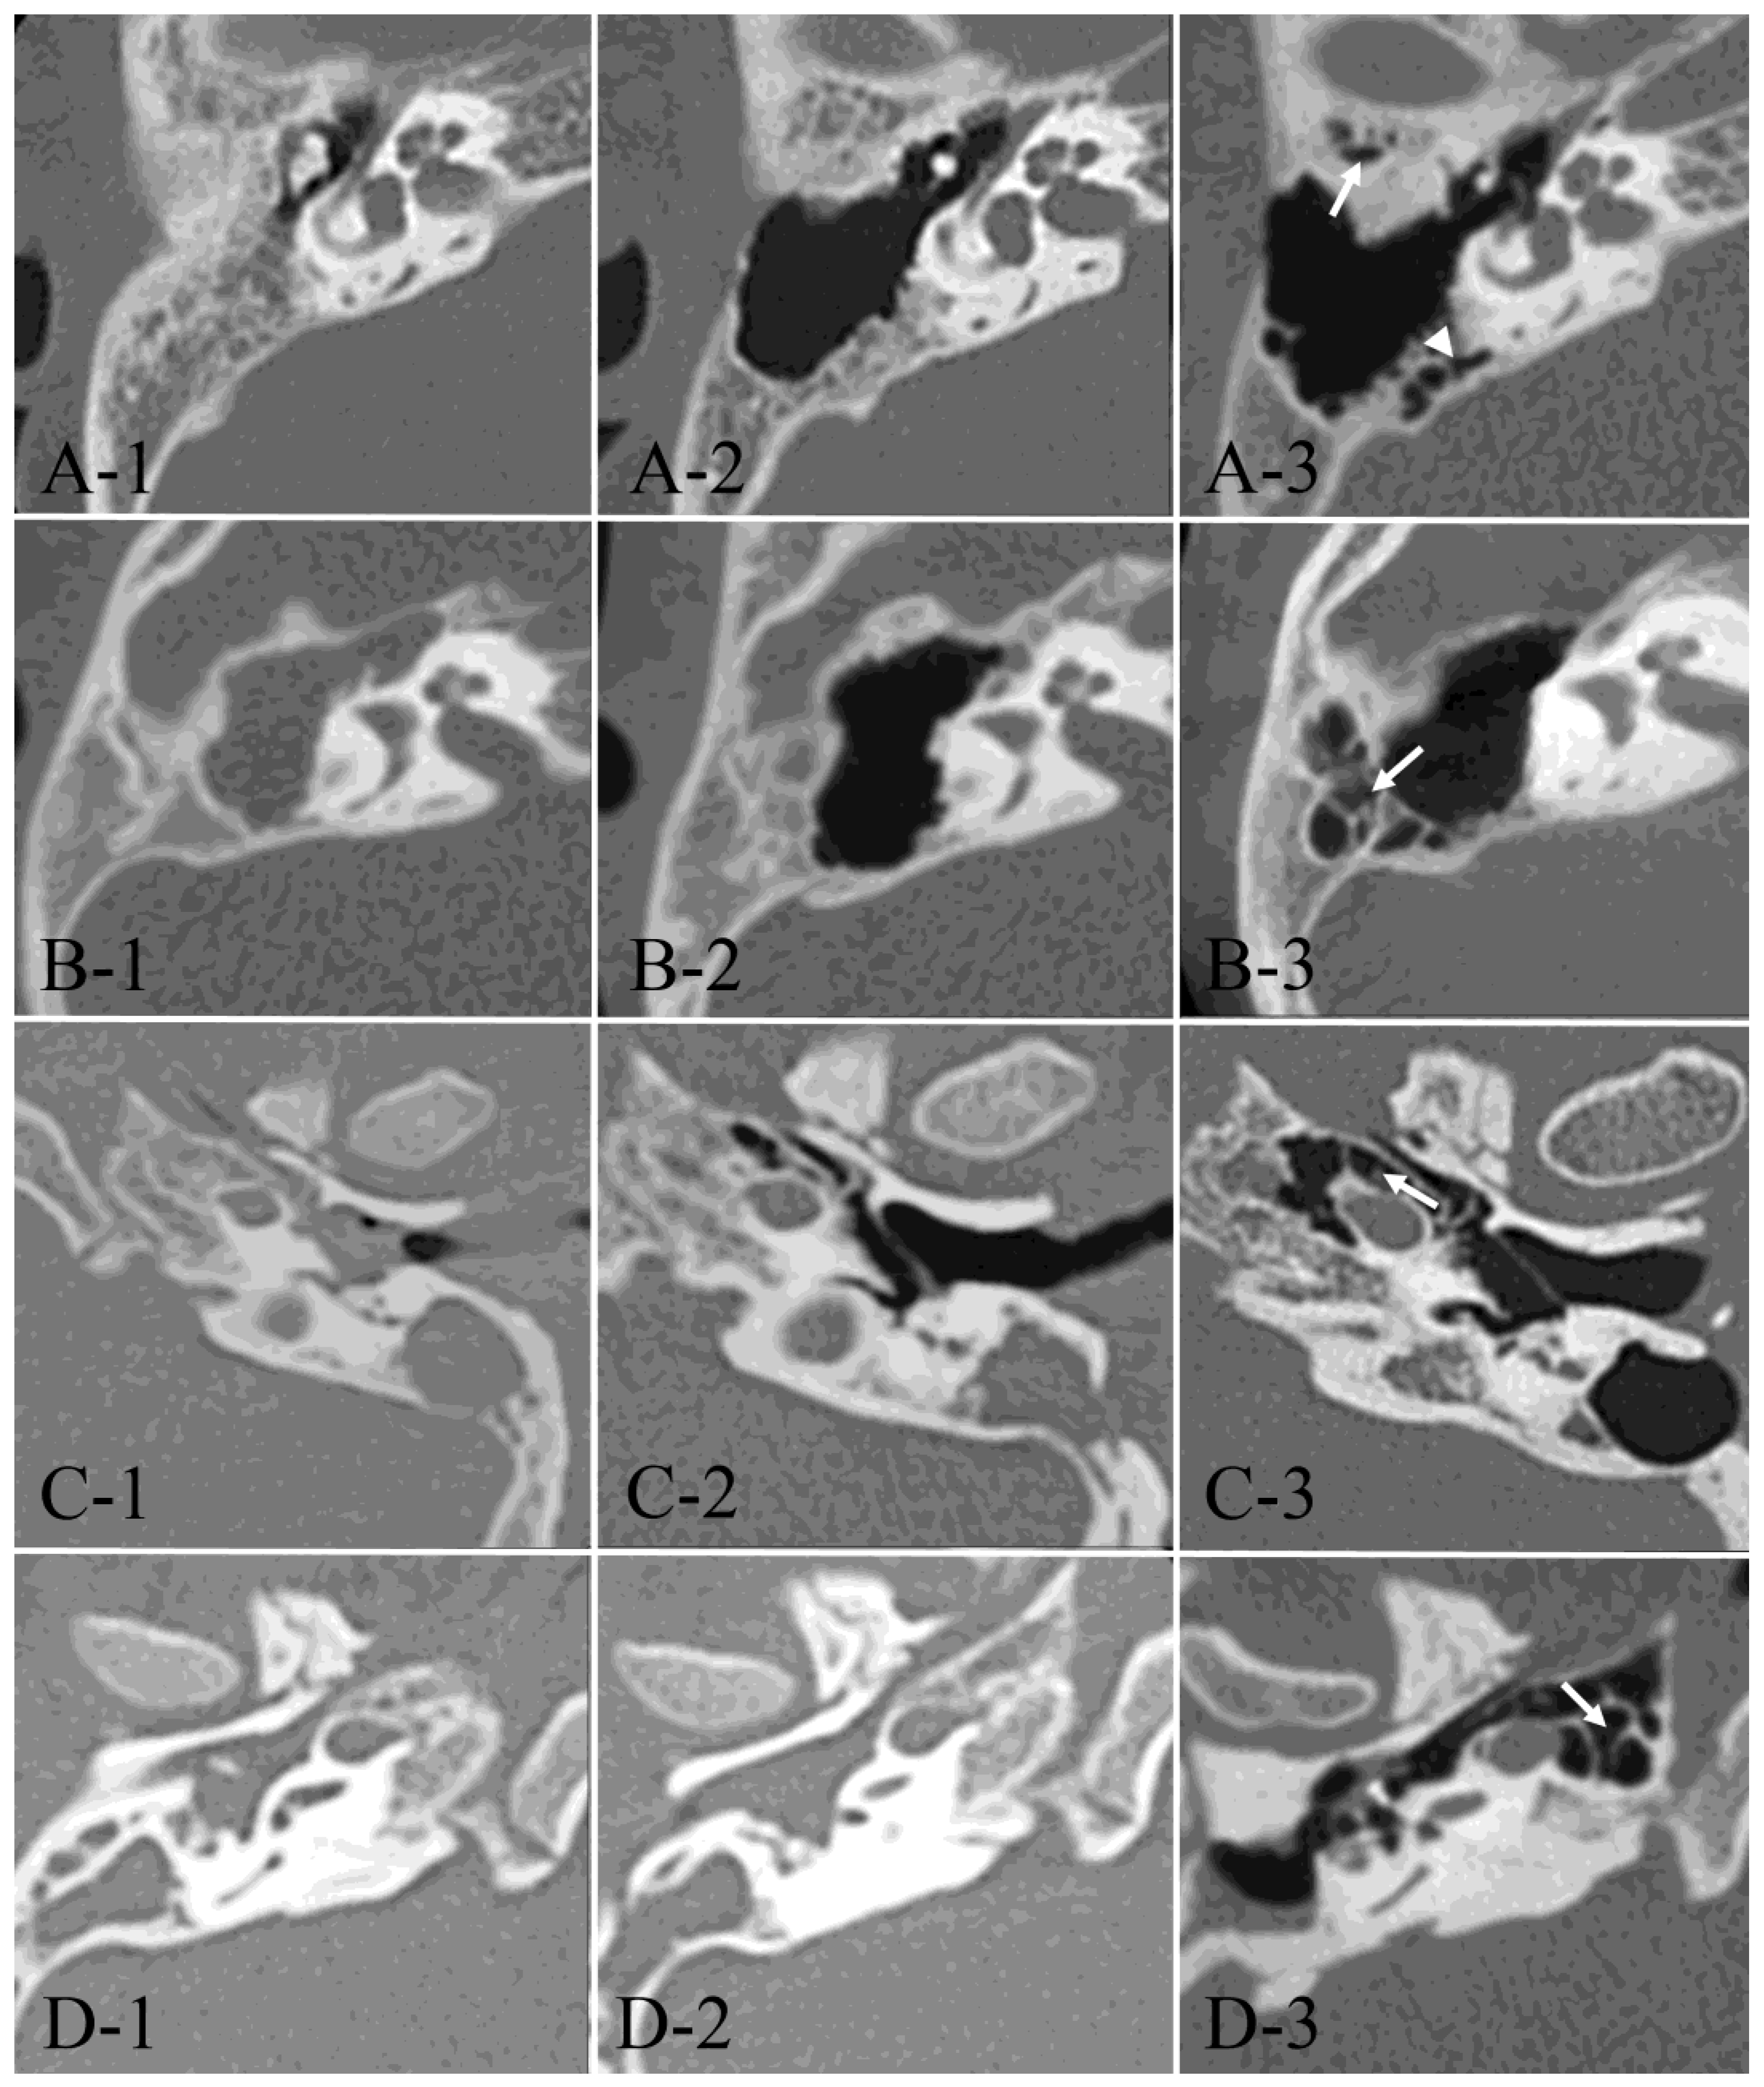

| ① | Anterolateral area of peri-antrum | 26/29 | (89.7%) | 26/29 | (89.7%) | 1.000 |

| ② | Posterolateral area of peri-antrum | 18/29 | (62.1%) | 26/29 | (89.7%) | 0.014 |

| ③ | Medial area of peri-antrum | 17/29 | (58.6%) | 28/29 | (96.6%) | <0.001 |

| ④ | Peritubal area | 16/29 | (55.2%) | 25/29 | (86.2%) | 0.009 |

| ⑤ | Petrous apex area | 7/29 | (24.1%) | 15/29 | (51.7%) | 0.030 |

| Acquired cholesteatoma (n = 34) | ||||||

| ① | Anterolateral area of peri-antrum | 21/34 | (61.8%) | 21/34 | (61.8%) | 1.000 |

| ② | Posterolateral area of peri-antrum | 24/34 | (70.6%) | 23/34 | (67.6%) | 1.000 |

| ③ | Medial area of peri-antrum | 11/34 | (32.4%) | 23/34 | (67.6%) | 0.007 |

| ④ | Peritubal area | 13/34 | (38.2%) | 24/34 | (70.6%) | 0.014 |

| ⑤ | Petrous apex area | 0/34 | (0%) | 3/34 | (8.8%) | 0.239 |